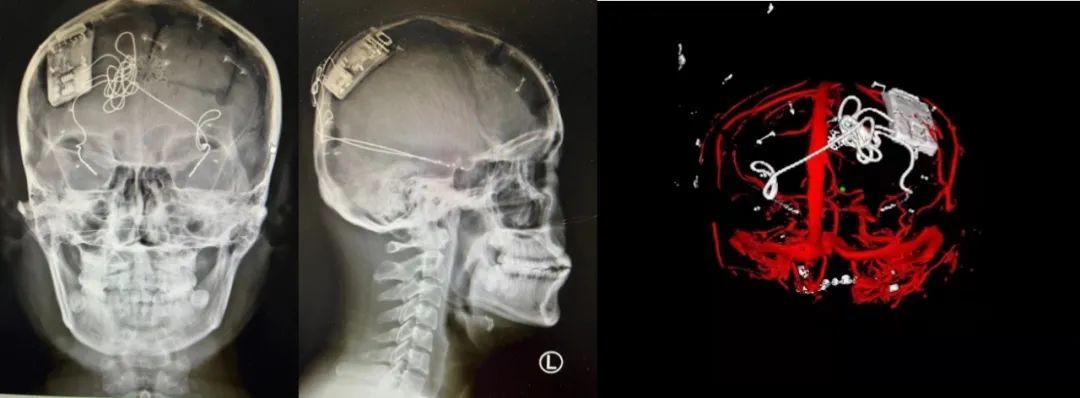

本次手術過程順利,術中刺激器各項指標均工作正常,術后重建顯示電極位置精準,腦電信號清晰。患者為男性,入院后診斷為雙側(cè)顳葉癲癇,此類癲癇為開顱手術的相對禁忌癥,在藥物無法控制的情況下,傳統(tǒng)治療效果欠佳 。

術前經(jīng)過宣武醫(yī)院癲癇多學科專家團隊詳細的臨床評估,包括視頻腦電監(jiān)測、頭顱磁共振及三維 CT 掃描、腦核醫(yī)學檢查等,全面評估了患者病情及致癇灶定位情況。

由于患者臨床診斷為雙側(cè)顳葉癲癇伴海馬硬化,無法通過致癇灶切除等傳統(tǒng)外科手術方式獲益,決定進行閉環(huán)反應性神經(jīng)刺激系統(tǒng)植入手術治療。并根據(jù)閉環(huán)神經(jīng)刺激技術特點,為患者“量身定制”植入方案,尤其是電極植入位點和脈沖發(fā)生器固定部位等,為手術的順利實施奠定了良好基礎。

團隊根據(jù)術前計劃,在手術機器人輔助下完成雙海馬長軸電極及 IPG 植入,術后重建顯示電極位置精準,腦電信號清晰。術后第二天,患者即下床活動,身體狀況恢復良好。